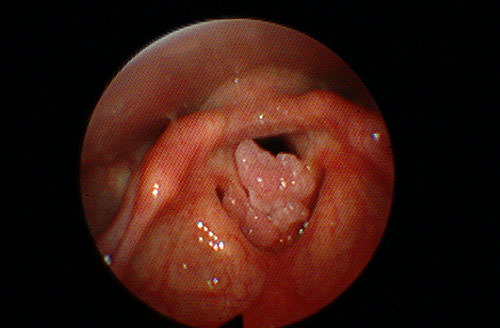

Djeca mogu biti promukla i zbog virusne infekcije na glasnicama (HPV) što se manistira rastom izraslina tj. papiloma